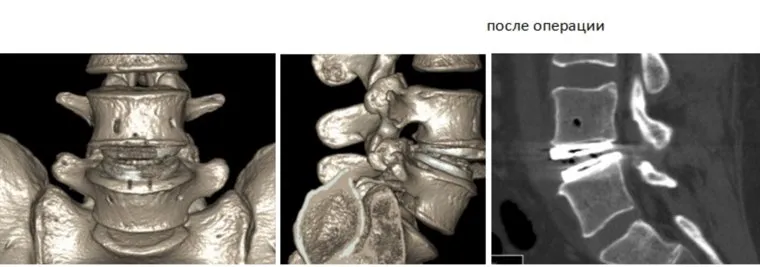

Пациенту сделали операцию и установили титановый протез поясничного диска в позвоночнике

Врачи-нейрохирурги Центра имени Илизарова провели уникальную операцию по установке протеза поясничного диска 32-летнему жителю из Москвы. Благодаря титановому импланту пациент не будет испытывать болей, когда ходит, лежит, стоит или наклоняется. Об этом сообщает пресс-служба медучреждения.

«Протез устанавливается далеко не всем. Среди показаний — дегенеративные заболевания позвоночника. После 40 лет нежелательно устанавливать данную конструкцию. Преимущественно — это должны быть пациенты молодого возраста, подростки, лица, ведущие активный образ жизни», — сообщили врач-вертебролог Клиники патологии позвоночника и редких заболеваний Полина Очирова. В рамках оказания высокотехнологичной медпомощи в Центре Илизарова уже проведено 10 операций по протезированию поясничного и шейного дисков для пациентов из разных регионов страны.